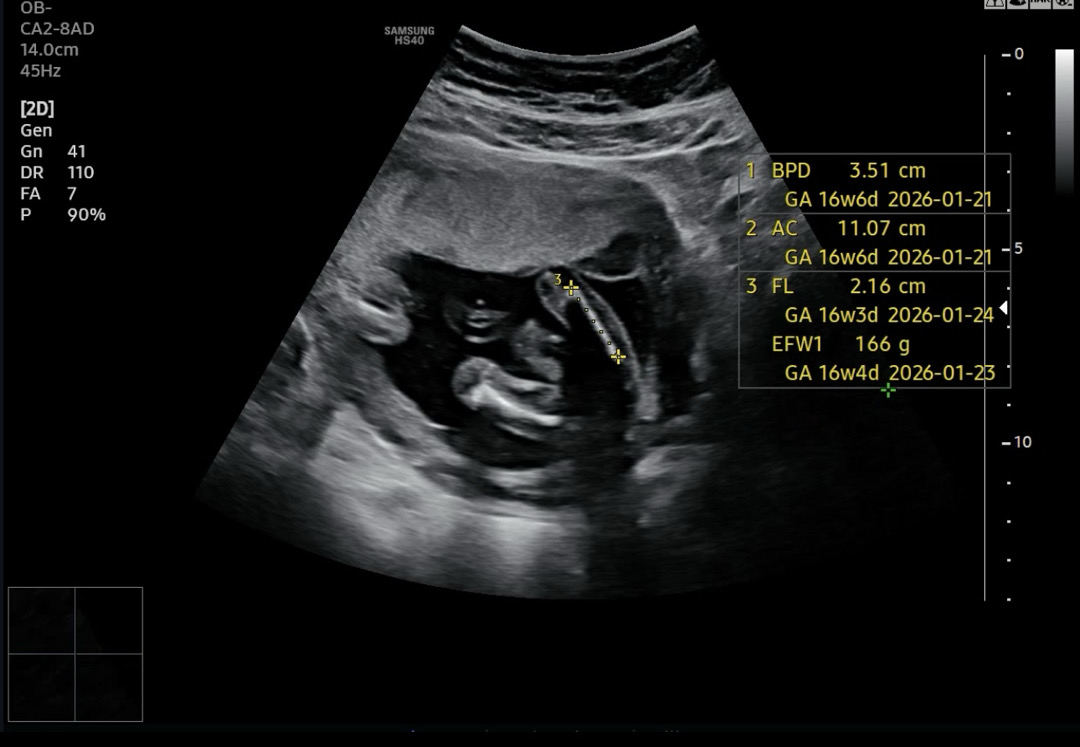

딸일까요 아들일까요?

오늘 2차 기형아 검사하고왔는데 교수님이 확정지어서 딸이다 아들이다 라고 안하시고 딸 가능성이 높다고 하셨는데 딸일까요 아들일까요?